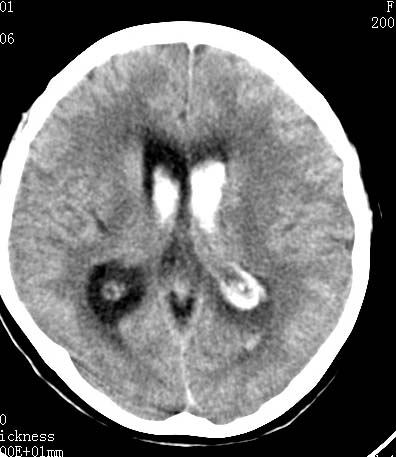

标题: CT9945:男性 病人 请大家看看出血的部位究竟在哪里? [打印本页]

标题: CT9945:男性 病人 请大家看看出血的部位究竟在哪里?

男性 病人 请大家看看出血的部位究竟在哪里?

是不是脑室系统出血啊! 伴轻度脑积水! 请老师指教!!

脑室系统出血,并脑积水.

我觉得是左侧侧脑室体旁出血,破入脑室系统.理由:除了左侧脑室体部外缘不规则之外,还有就是左侧脑室里面出血量较右侧多!

应该是左侧侧脑室内的出血导致其他脑室内的积血。

应该是尾状核出血破入侧脑室.

1、原发脑室出血,出血部位应该是左侧侧脑室;

脑室系统出血,第三脑室,侧脑室都有

左侧尾状核体部出血破入脑室系统.

最重要的是要讲明以脑室内积血为主,脑积水